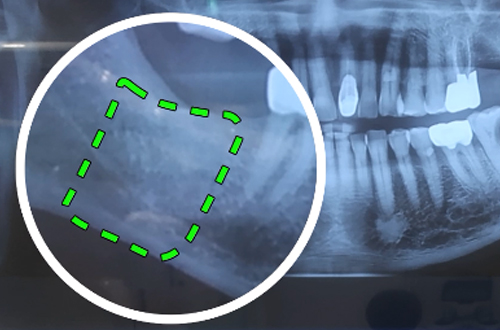

CT촬영을 판독해본 결과 뼈의 높이와 폭이 충분하다고 판단이 되어 무피판 임플란트 수술을 진행하였습니다.

잇몸의 두께가 충분하여 잇몸 절개 없이 임플란트를 식립해 드렸으며 힐링어버트먼트라고 하는 것을 장착해서 잇몸이 잘 치유가 될 수 있도록 하였습니다.